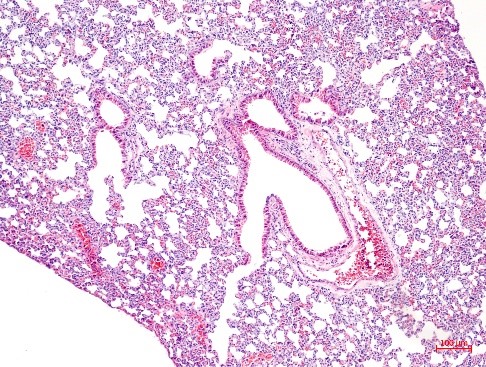

1、HE染色实验结果(小鼠肝脏-肺脏-心肌举例)

HE实验结果解读:细胞核呈现蓝色或者紫蓝色,细胞质和细胞外基质中的成分着红色。